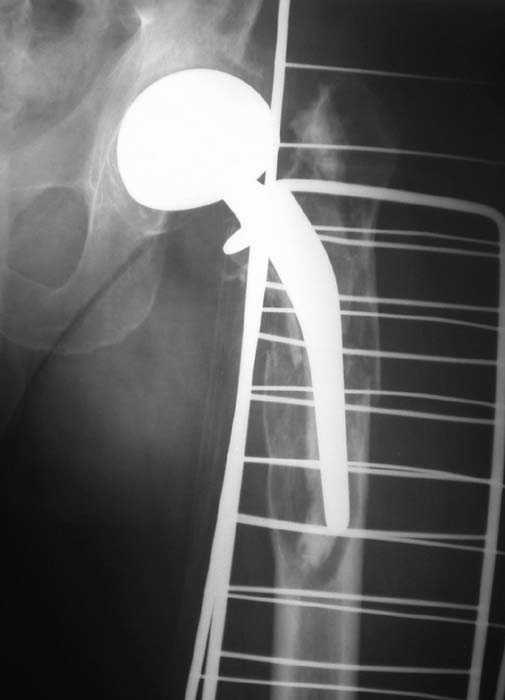

Мужчина, 39 лет.По поводу двустороннего асептического некроза головок бедренных костей последовательно выполнено тотальное эндопроезирование левого (1998 г), затем правого (1999 г) тазобедренных суставов.

С 2001 г отмечает нарастающие боли в левом бедре. Предполагается удаление протеза, удаление цемена из канала бедра, пластика дефекта бедренной кости.

Вторым этапом - тотальное бесцементное протезирование. Ваши предложения, мнения?

Нет никакого смысла делать операцию в два этапа. С чашкой все понятно - стандартный подход с установкой пресс-фит компонента. На бедре имеет

место перипротезный перелом В3 типа - т.е. перелом вокруг ножки с ее нестабильностью на фоне выраженного остеолиза. Решение - доступ к каналу

через перелом с удалением самой ножки, костного цемента и рубцовых тканей. Установка ножки дистальной фиксации (типа Solution), длину ножки

надо определить по шаблону. Минимальный контакт ножки с интактной костью - 6-8 см. Фрагменты проксмального отдела собираются на ножке

эндопротеза, дефекты костной ткани заполняются чипсами (аллографт) и фиксируются кортикальными аллографтами, уложенными дополнительно по типу

"вязанки хвороста" серкляжом. Мы имеем 8 или 10 подобных наблюдений и результатами довольны.

Абсолютно согласен.Это проверенный путь.Единственное, под Solution надо тщательно удалить цемент из бедра куда встанет дистальная часть ножки.Иначе при установке расколите диафиз бедра.Было поначалу такое у нас.С уважением